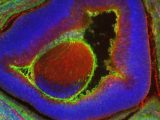

世界最古の防衛・安全保障分野のシンクタンクである「英国王立防衛安全保障研究所(RUSI)」によると、中国は遺伝子組み換えで強化した兵士の軍団を作ろうとしているという。それは恐ろしい「ターミネーター兵士」で、強くたくましい体を持ち知力も高い上、優れた聴覚や暗闇でも見える視覚を備え、怪我からの回復も早く、戦場では痛みすら感じないという。

同様の試みは西側諸国でも検討されているが、現在の遺伝子編集技術を人間に応用することはハードルが非常に高い。だが、中国では2018年に賀建奎氏による遺伝子編集ベビーがすでに誕生している。無論、このような実験は中国でも違法であり、賀氏は現在投獄中とされているが、世界的に見ても貴重なそのノウハウが、秘密裏に軍事へ応用されているとしても全く不思議ではない。

RUSIのジョン・ラウス氏も、遺伝子組み換え技術の人間への応用は可能と見ている。そして実際、中国の上層部は人間の遺伝子組み換えという恐るべき試みに対し積極的であり、前線にいる兵士を強化すると考えるのは合理的であると指摘している。